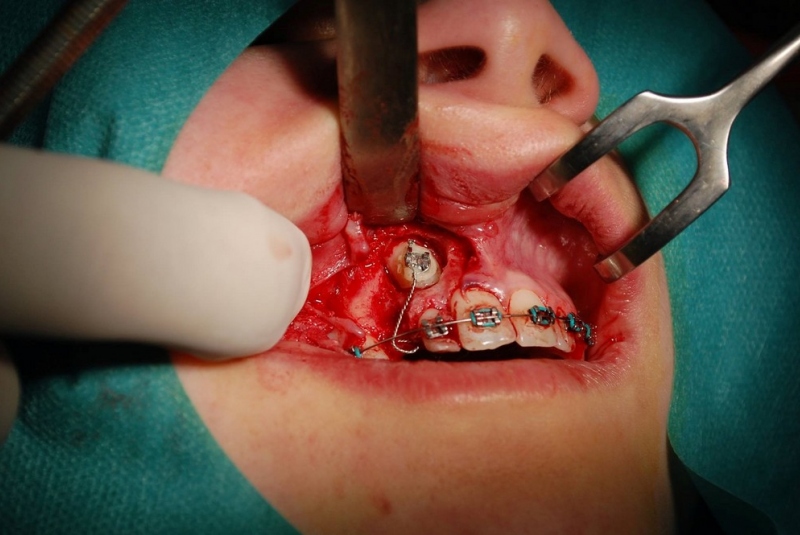

- Patefakcia (čeľustno-ortotodontické sťahovanie, zle postave- ných zubov do oblúka)

- Chirurgické extrakcie